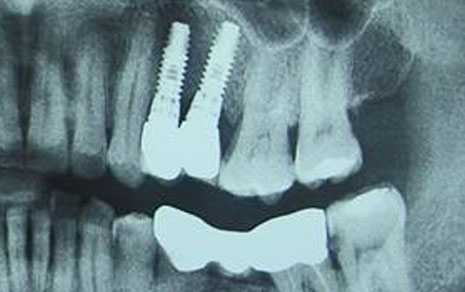

Multiple Implants

Restore several teeth while maintaining chewing function and jaw health.

All-on-4 Implants

Full-arch restoration using just 4 implants, often completed in a few days.